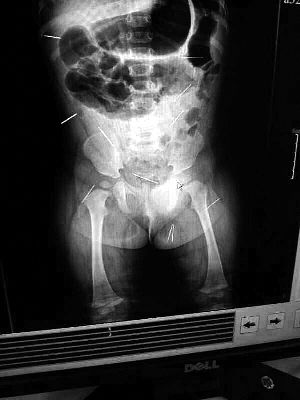

山東聊城11個月女嬰萱萱(化名)疑似被人以12根鋼針插滿臀部、腹腔等部位,昨天在兒童醫院會診后,醫生稱3根針靠近胸腔最危險,首批先行取出,預計將在下周二手術。孩子父母稱孩子一直由家人照顧,自家與他人并無冤怨。山東警方表示正在偵破中,不便透露案情。

“要不是當初那幾個紅點,可能到現在我們還不知道孩子身體里有鋼針!”昨天,在兒童醫院住院處,萱萱爸爸范先生稱,日前原本很愛笑的萱萱突然變得有些焦躁,一抱起來就哭,孩子母親偶然間在萱萱屁股上發現了幾個小紅點兒,原以為是蚊蟲叮咬,就醫結果卻讓人不寒而栗。“醫院拍出的片子上,萱萱的體內有12根鋼針,插滿臀部、腹腔、骨盆等各個部位。”范先生介紹,因為鋼針已深入體內,要是孩子不哭鬧,他們很難發現。

北京晨報記者了解到,目前體內的12根鋼針多分布在孩子的臀部,一根在腹部,其余3根在胸腔附近,其中一根很接近心臟。“因為孩子太小,醫生們害怕取針的時候對她造成傷害,在胸腔附近的3針可能會威脅她的生命”。